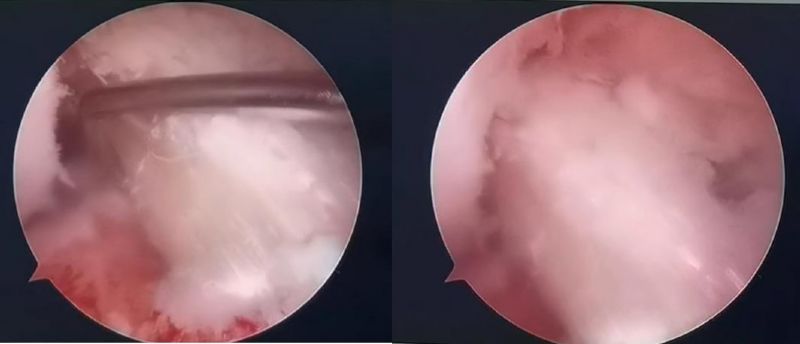

經(jīng)患者同意后,李鵬主任手術團隊制定詳細手術方案。手術如期進行,經(jīng)團隊密切配合,對幾位患者分別順利完成關節(jié)鏡下膝關節(jié)鏡鏡檢、關節(jié)清理、股薄肌半腱肌取腱移植術、前交叉韌帶重建術、軟骨損傷微骨折術、半月板縫合修整術等。

鏡下重建前交叉韌帶走形、張力良好